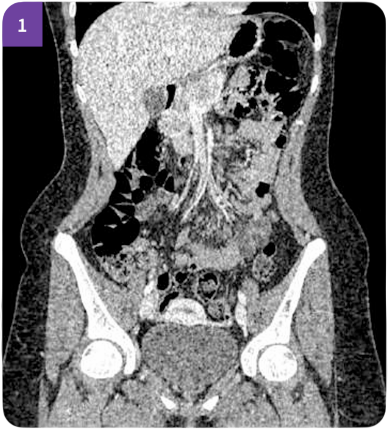

В клинической практике металлические конструкции часто создают выраженные артефакты на КТ изображениях. Это может затруднять оценку окружающих тканей и снижать информативность томографии. В системе реализована технология Smart MAR (Metal Artifact Reduction), предназначенная для уменьшения артефактов от металлических объектов при выполнении исследования.

Алгоритм анализирует данные реконструкции и корректирует области, где возникают искажения из-за высокоплотных материалов. В результате уменьшается выраженность полосовых артефактов и улучшается визуализация анатомических структур рядом с имплантами и протезами.

Smart MAR уменьшает выраженность полосовых артефактов, сохраняя структурную детализацию костей и мягких тканей. Слева без MAR, справа с MAR